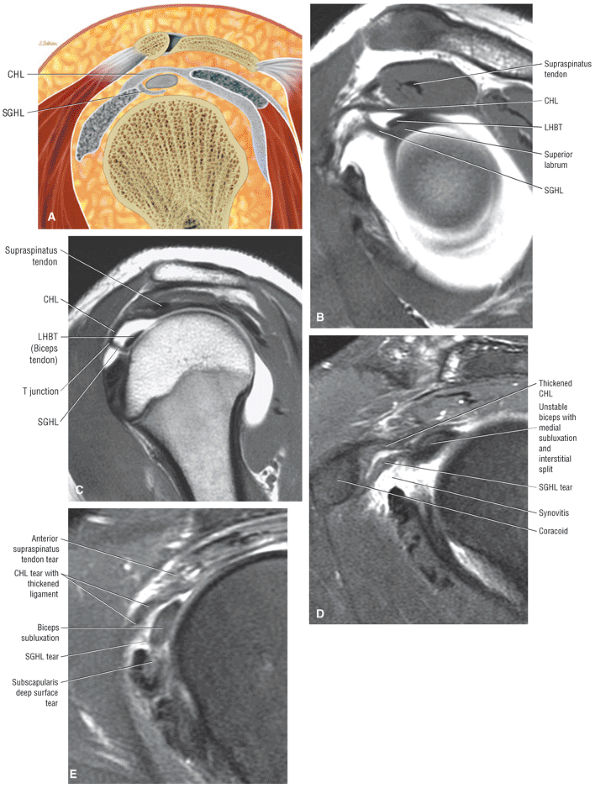

The rotator cuff interval is located between the superior aspect of the subscapularis tendon and the inferior aspect of the supraspinatus tendon. This interval contains the coracohumeral ligament and the SGHL. A hidden lesion of the rotator interval has been attributed to pathology of the CHL–SGHL confluence, which forms the biceps sling or pulley. Surgical closure of the interval appears to eliminate excessive inferior translation.59